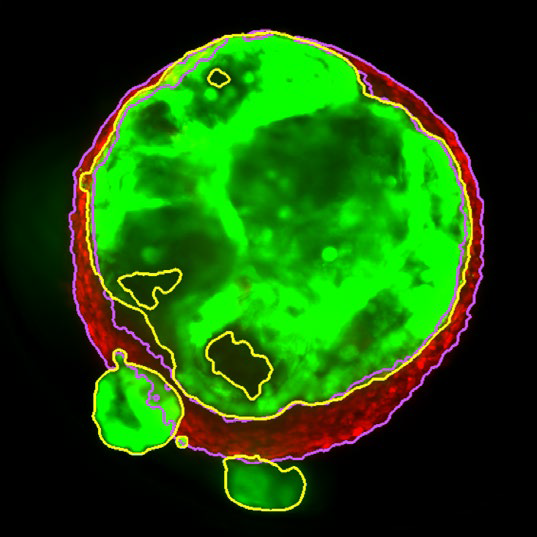

Figure 2. MaxIP image of 3D tumor co-culture microtissue - NCI-N87-GFP (gastric carcinoma; green) and NIH-RFP (murine fibroblast; red). Image Credit: Yokogawa Life Science

Figure 3. Z slice of the tumor microtissue treated with 0.05 % DMSO - tumor (yellow region) and fibroblast (purple region) are recognized separately in 3D. Image Credit: Yokogawa Life Science

Tumor spheroids were created by seeding an Akura™ 384 plate with a monodispersed mixture of GFP-expressing NCI-N87 (gastric carcinoma) and RFP-expressing NIH3T3-L1 (murine fibroblast) cells, which spontaneously formed spheroids through scaffold-free self-assembly over several days. After spheroid formation, selected wells containing tumor spheroids were treated with DMSO at 0.05, 0.5, or 5.0 μM Lapatinib for six days. The images were analyzed in 3D, with NCI-N87-GFP (tumor) and NIH-RFP (fibroblast) identified separately, and the volume of each spheroid measured.